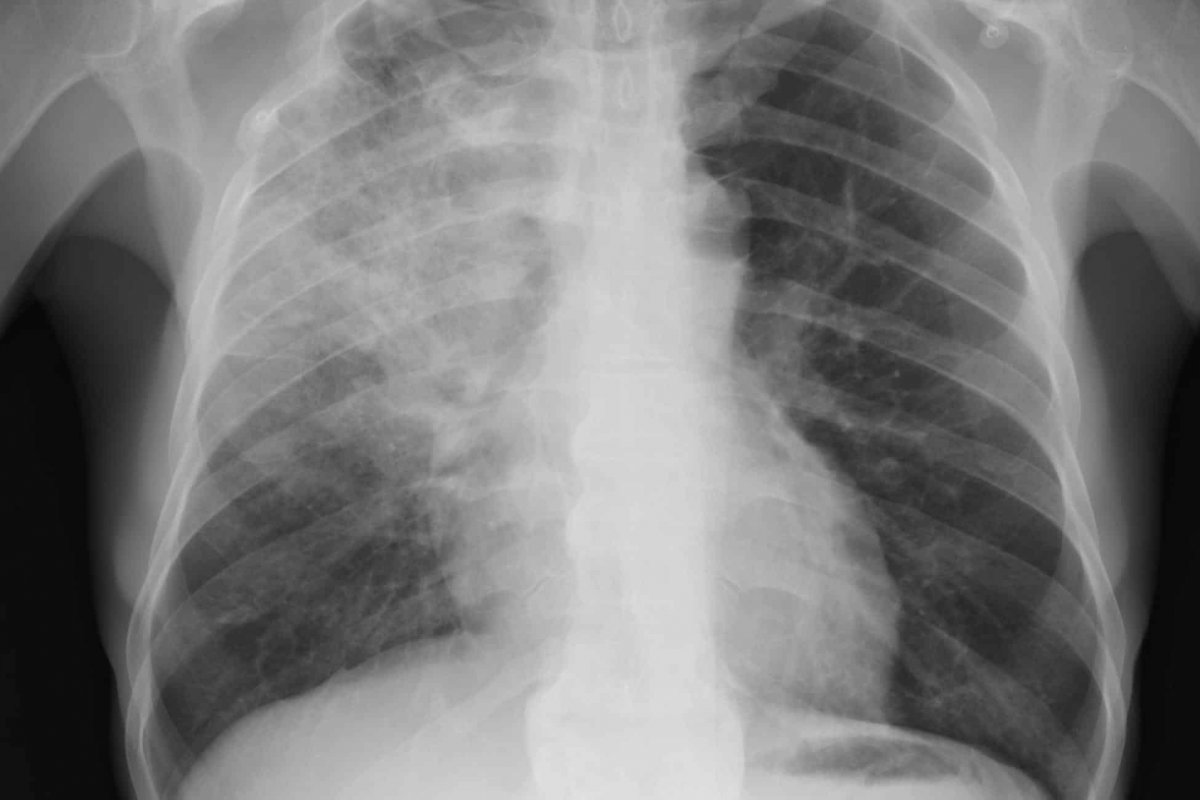

Foto: Reprodução/Olhar Digital

Os médicos Hospital Universitário de Quioto, no Japão, anunciaram o sucesso do primeiro transplante de tecido pulmonar de doadores vivos para uma paciente com grave lesão pulmonar causada pela Covid-19 na história nesta quarta-feira (7). A paciente, uma mulher da região oeste de Kansai, permaneceu na mesa de cirurgia por quase 11 horas para receber a doação de parte dos pulmões do seu marido e do seu filho.